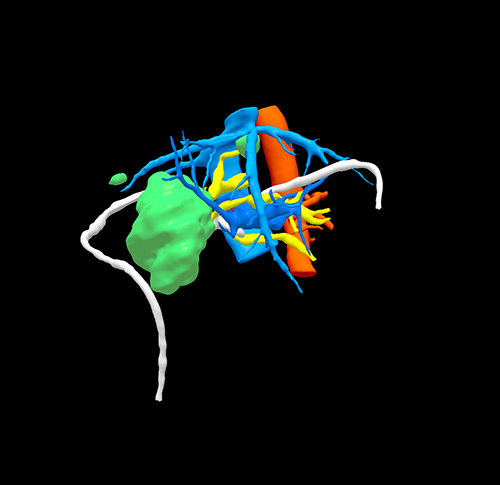

右肝胆管细胞癌、胆道梗阻---右三肝切除、左肝管空肠Roux-en-Y切除